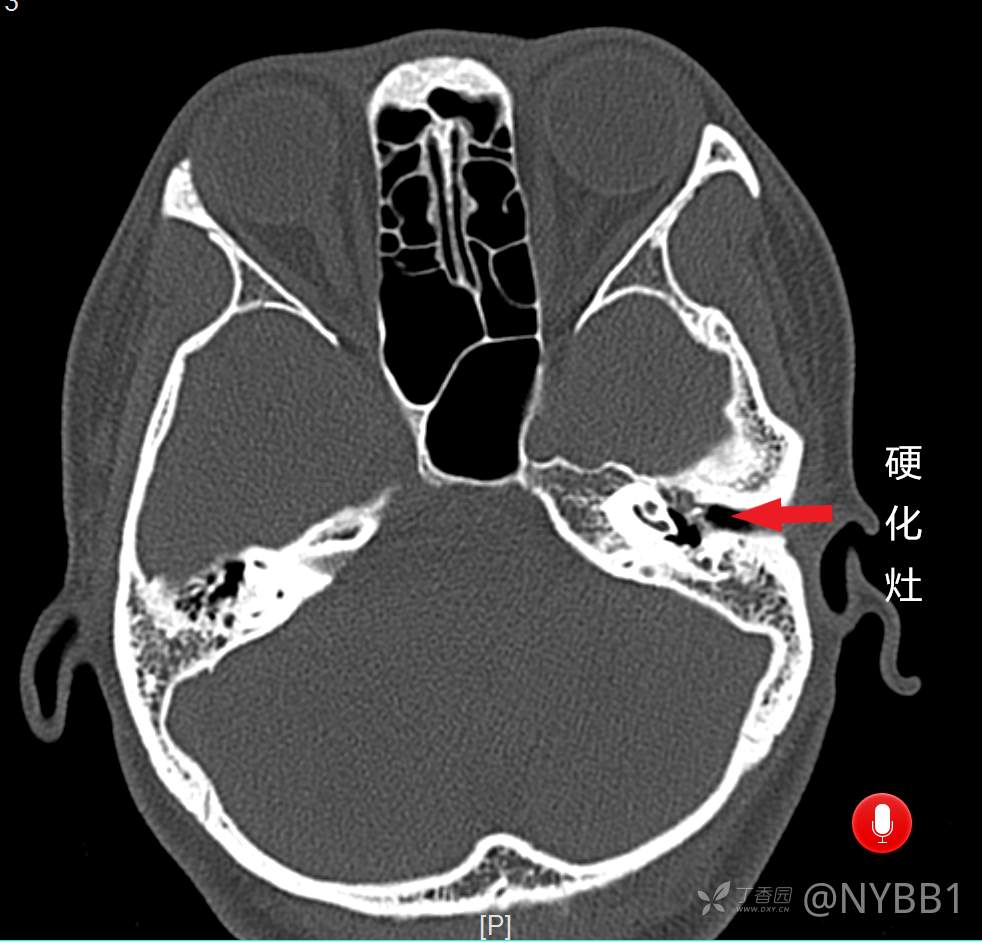

患者外耳道狭窄,鼓膜前端器械无法触及,在无持续灌流模式下行“耳内镜下外耳道扩大+鼓室成形”。